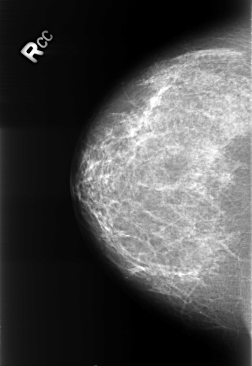

Volume: benign_without_callback_01 Case: B-3245-1

B_3245_1.RIGHT_CC

filename B-3245-1

DATE_OF_STUDY 11 8 1998

PATIENT_AGE 48

DENSITY 2

RIGHT_CC LINES 4392 PIXELS_PER_LINE 3016 BITS_PER_PIXEL 12 RESOLUTION 50 NON_OVERLAY

FILE: B_3245_1.LEFT_CC.OVERLAY

TOTAL_ABNORMALITIES 1

ABNORMALITY 1

LESION_TYPE CALCIFICATION TYPE LUCENT_CENTER DISTRIBUTION N/A

ASSESSMENT 2

SUBTLETY 5

PATHOLOGY BENIGN_WITHOUT_CALLBACK

TOTAL_OUTLINES 1